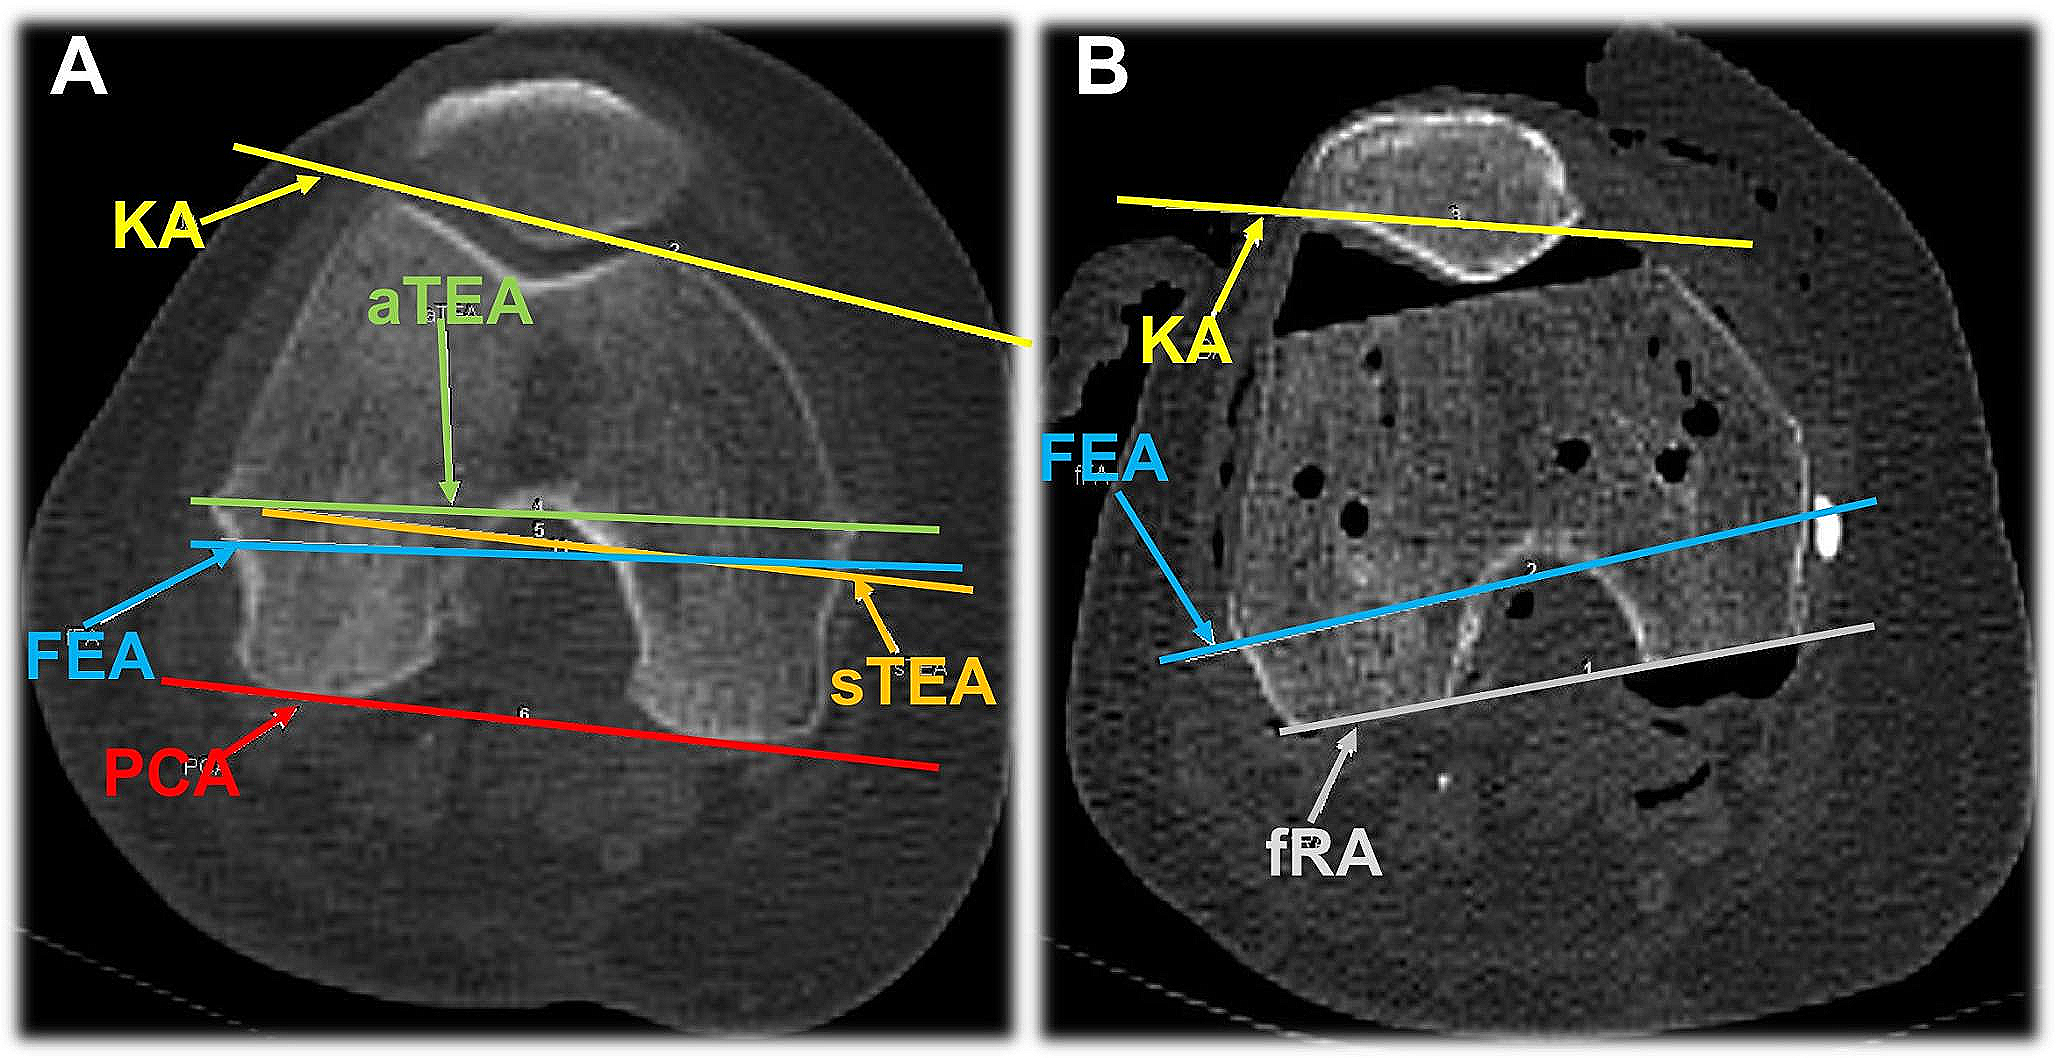

To measure the individual angles, an axial section plane was first determined in which the anatomical axes (aTEA, sTEA, PCA) could be drawn according to their bony landmarks. For comparison, the FEA had to be transferred to the respective section plane according to its angle to the K-wire axis and drawn in. In the preoperative CT, the individual angles of the aTEA, sTEA, PCA and FEA to this axis were determined (see Fig. 3A).

Fig. 3

Axial CT imaging of the knee. (A) Preoperative determination of anatomic axes. KA = K-wire axis, aTEA = anatomic transepicondylar axis, sTEA = surgical transepicondylar axis, FEA = flexion-extension axis, and PCA = posterior condylar axis. (B) Postoperative axis determination. KA = K-wire axis, FEA = flexion-extension axis and fRA = functional rotation axis

Bild vergrößern

The functional axis of rotation (fRA) was determined on postoperative CT imaging (see Fig. 3B), corresponding to the dorsal resection area on the femur. In addition, the angle to the K-wire axis (KA) was measured (see Fig. 3). After determining the individual axes or their angles to each other, the axes of the aTEA, sTEA, PCA and the fRA were compared to the flexion-extension axis (FEA) which represents the physiological flexion-extension axis that was set equal to zero. In addition, for axis deviations into external rotation, the respective angle was marked by a positive sign, while for axis deviations into internal rotation, it was marked by a negative sign.